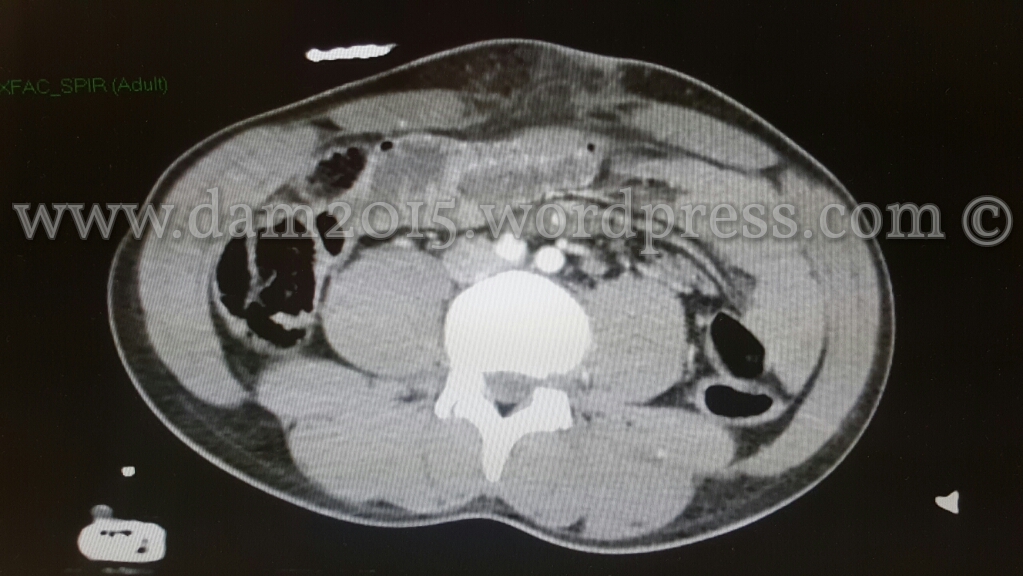

Peggioramento del quadro clinico addominale.

Eseguita nuova TC addome che mostrava incremento dell’imbibizione edematosa-emorragica del tessuto adiposo sottocutaneo e comparsa di marcato ispessimento edematoso delle anse del piccolo intestino ove sembrava apprezzarsi discontinuità della parete intestinale; presenza di bolle di aria libera come per perforazione di viscere cavo.